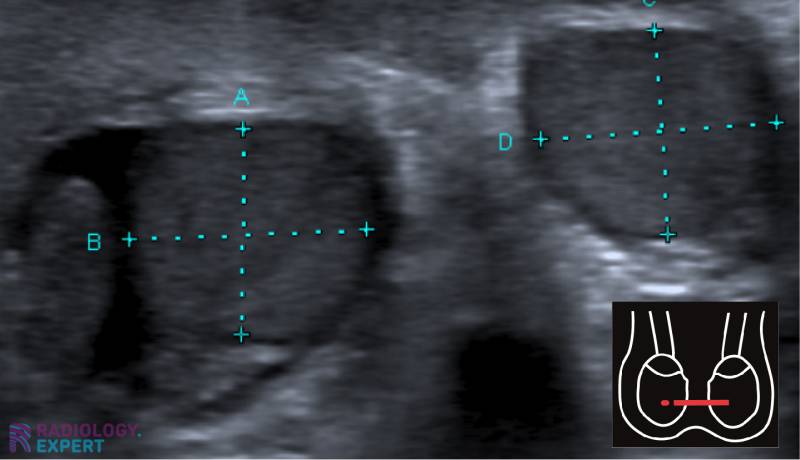

Background: Ultrasonography (US) represents the gold standard imaging method for the assessment of testicular lesions (TL). The gray-scale (GSUS) and color-Doppler (CDUS) ultrasound examination allow sonographers to investigate size, margins, echotexture and vascular features of TL, with the effort to differentiate benign from malignant lesions. Recently, the use Testicular Ultrasound FAQOne of our most commonly-requested medical ultrasounds by GPs is our Testicular/Scrotal Ultrasound. We often find that it can be

Read everything about what the ultrasound scrotal examination has to offer; from diagnosing something relatively harmless (such as hydrocele) to an emergency indication such as torsio testis. Some of the keypoints are epidimysis, torsio testis, varicocéle and hydrocéle Prior to this module, it is wise to read the Ultrasound Technique module. This module consists of the

Multiparametric Ultrasound for Diagnosing Testicular Lesions: Everything You Need to Know in Daily Clinical Practice Article Full-text available Nov 2023 scrotal ultrasound volume 4Skip the cable setup & start watching YouTube TV today for free. Then save $23/month for 2 mos. 1 Review Multiparametric Ultrasound for Diagnosing Testicular Lesions: Everything You Need to Know in Daily Clinical Practice Short title: multiparametric ultrasound and testicular lesions